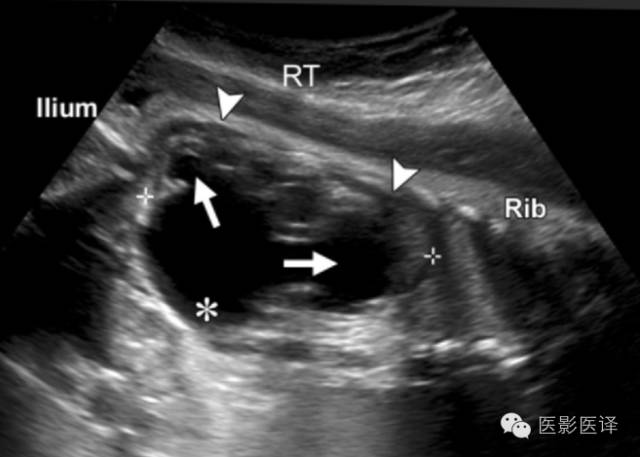

肾盂积水

胎儿肾盂积水,可清晰看到肾盏与肾盂相通(图10)。周围肾实质可能回声正常、变薄、回声增强或者发展为阻塞性囊性发育不良。肾盂积水的位置邻近于脊柱,这有助于与其他腹部肿块如卵巢囊肿进行鉴别。大多数胎儿肾盂积水是轻度的,Sairam等将肾盂前后径4-7mm定义为轻度积水。大多数病例会在产前及产后自发地好转,极少数病例需要外科干预。然而,诸多产后疾病的发生风险,包括肾盂输尿管交界处阻塞、输尿管阻塞、梨状腹综合征、VATER综合征(脊椎缺陷、肛门闭锁,合并食管闭锁的气管食管瘘,肾和桡骨异常),孤立肾、肾肿瘤等,会随着肾盂积水严重程度的增加而增加。

图10.肾盂积水。胎儿的纵向超声图像显示显著的肾盂积水,积水继发于肾盂输尿管交界处梗阻。注意那些与肾盂(*)相通的扩张的肾盏(箭)。肾实质的厚度(箭头)比卵巢囊肿壁厚的多。RT=右侧